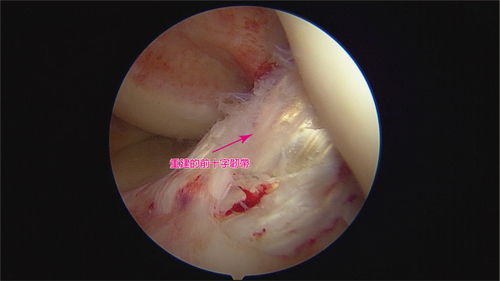

目前手術治療包括物理性增強與生物性增強。傳統韌帶修補或重建手術對病人來說主要是物理性增強的治療,生物性增強就是自體血小板注射(PRP),或運用自體脂肪膠質幹細胞治療(SVF)。但劉冠麟主任強調,治療的結果往往和病人的配合度相關,經過手術可以保護受傷膝關節內的十字韌帶,但周遭肌肉也會因受傷而萎縮沒力,因此治療成功的關鍵不只需要一個成功骨科手術,還包括術後自我保護、與後續持續的增能復健增強肌力。

加速前十字韌帶修復,也可用自體脂肪膠質幹細胞治療(SVF),圖中為其他病人SVF手術時的照片。